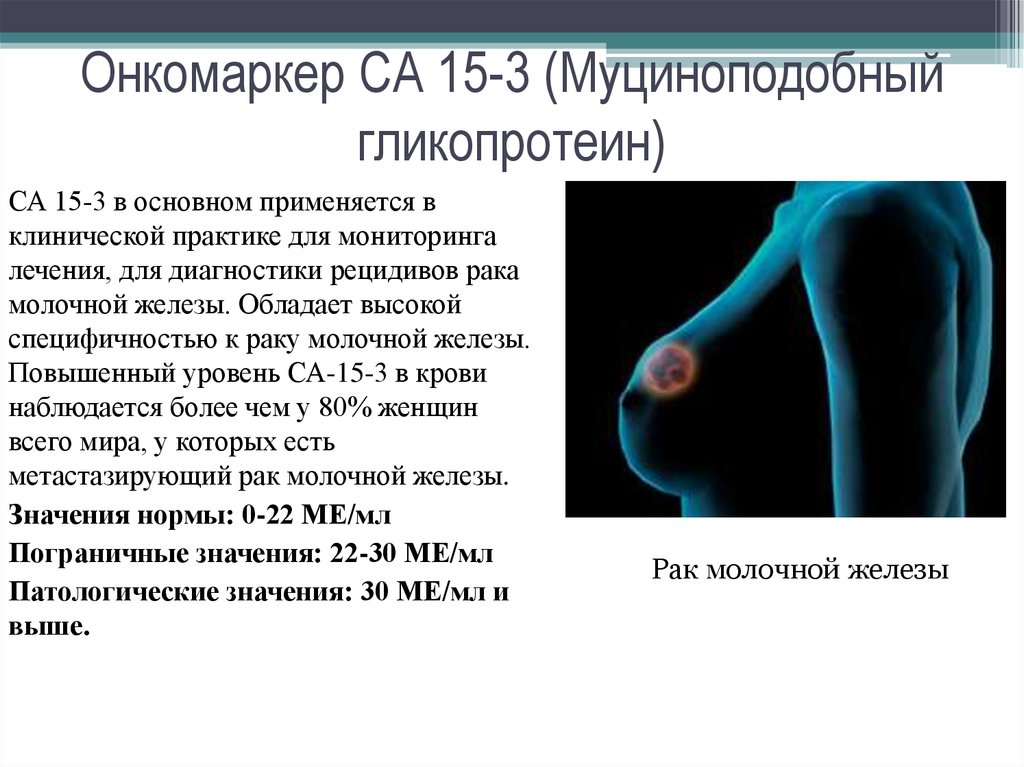

Фиброламеллярная карцинома печени мрт. Фиброламеллярная карцинома печени кт. Доброкачественная опухоль печени мрт. Гепатоцеллюлярная карцинома мрт. Онкомаркеры локализация опухоли. Онкомаркеры презентация. Онкомаркеры в онкологии. Анализ на онкомаркер.

Онкомаркеры локализация опухоли. Онкомаркеры презентация. Онкомаркеры в онкологии. Анализ на онкомаркер. Нейроэндоскопия головного мозга. Хирургическая операция на головном мозге. Эндоскопические операции на головном мозге. Хирургическое вмешательство в мозг.